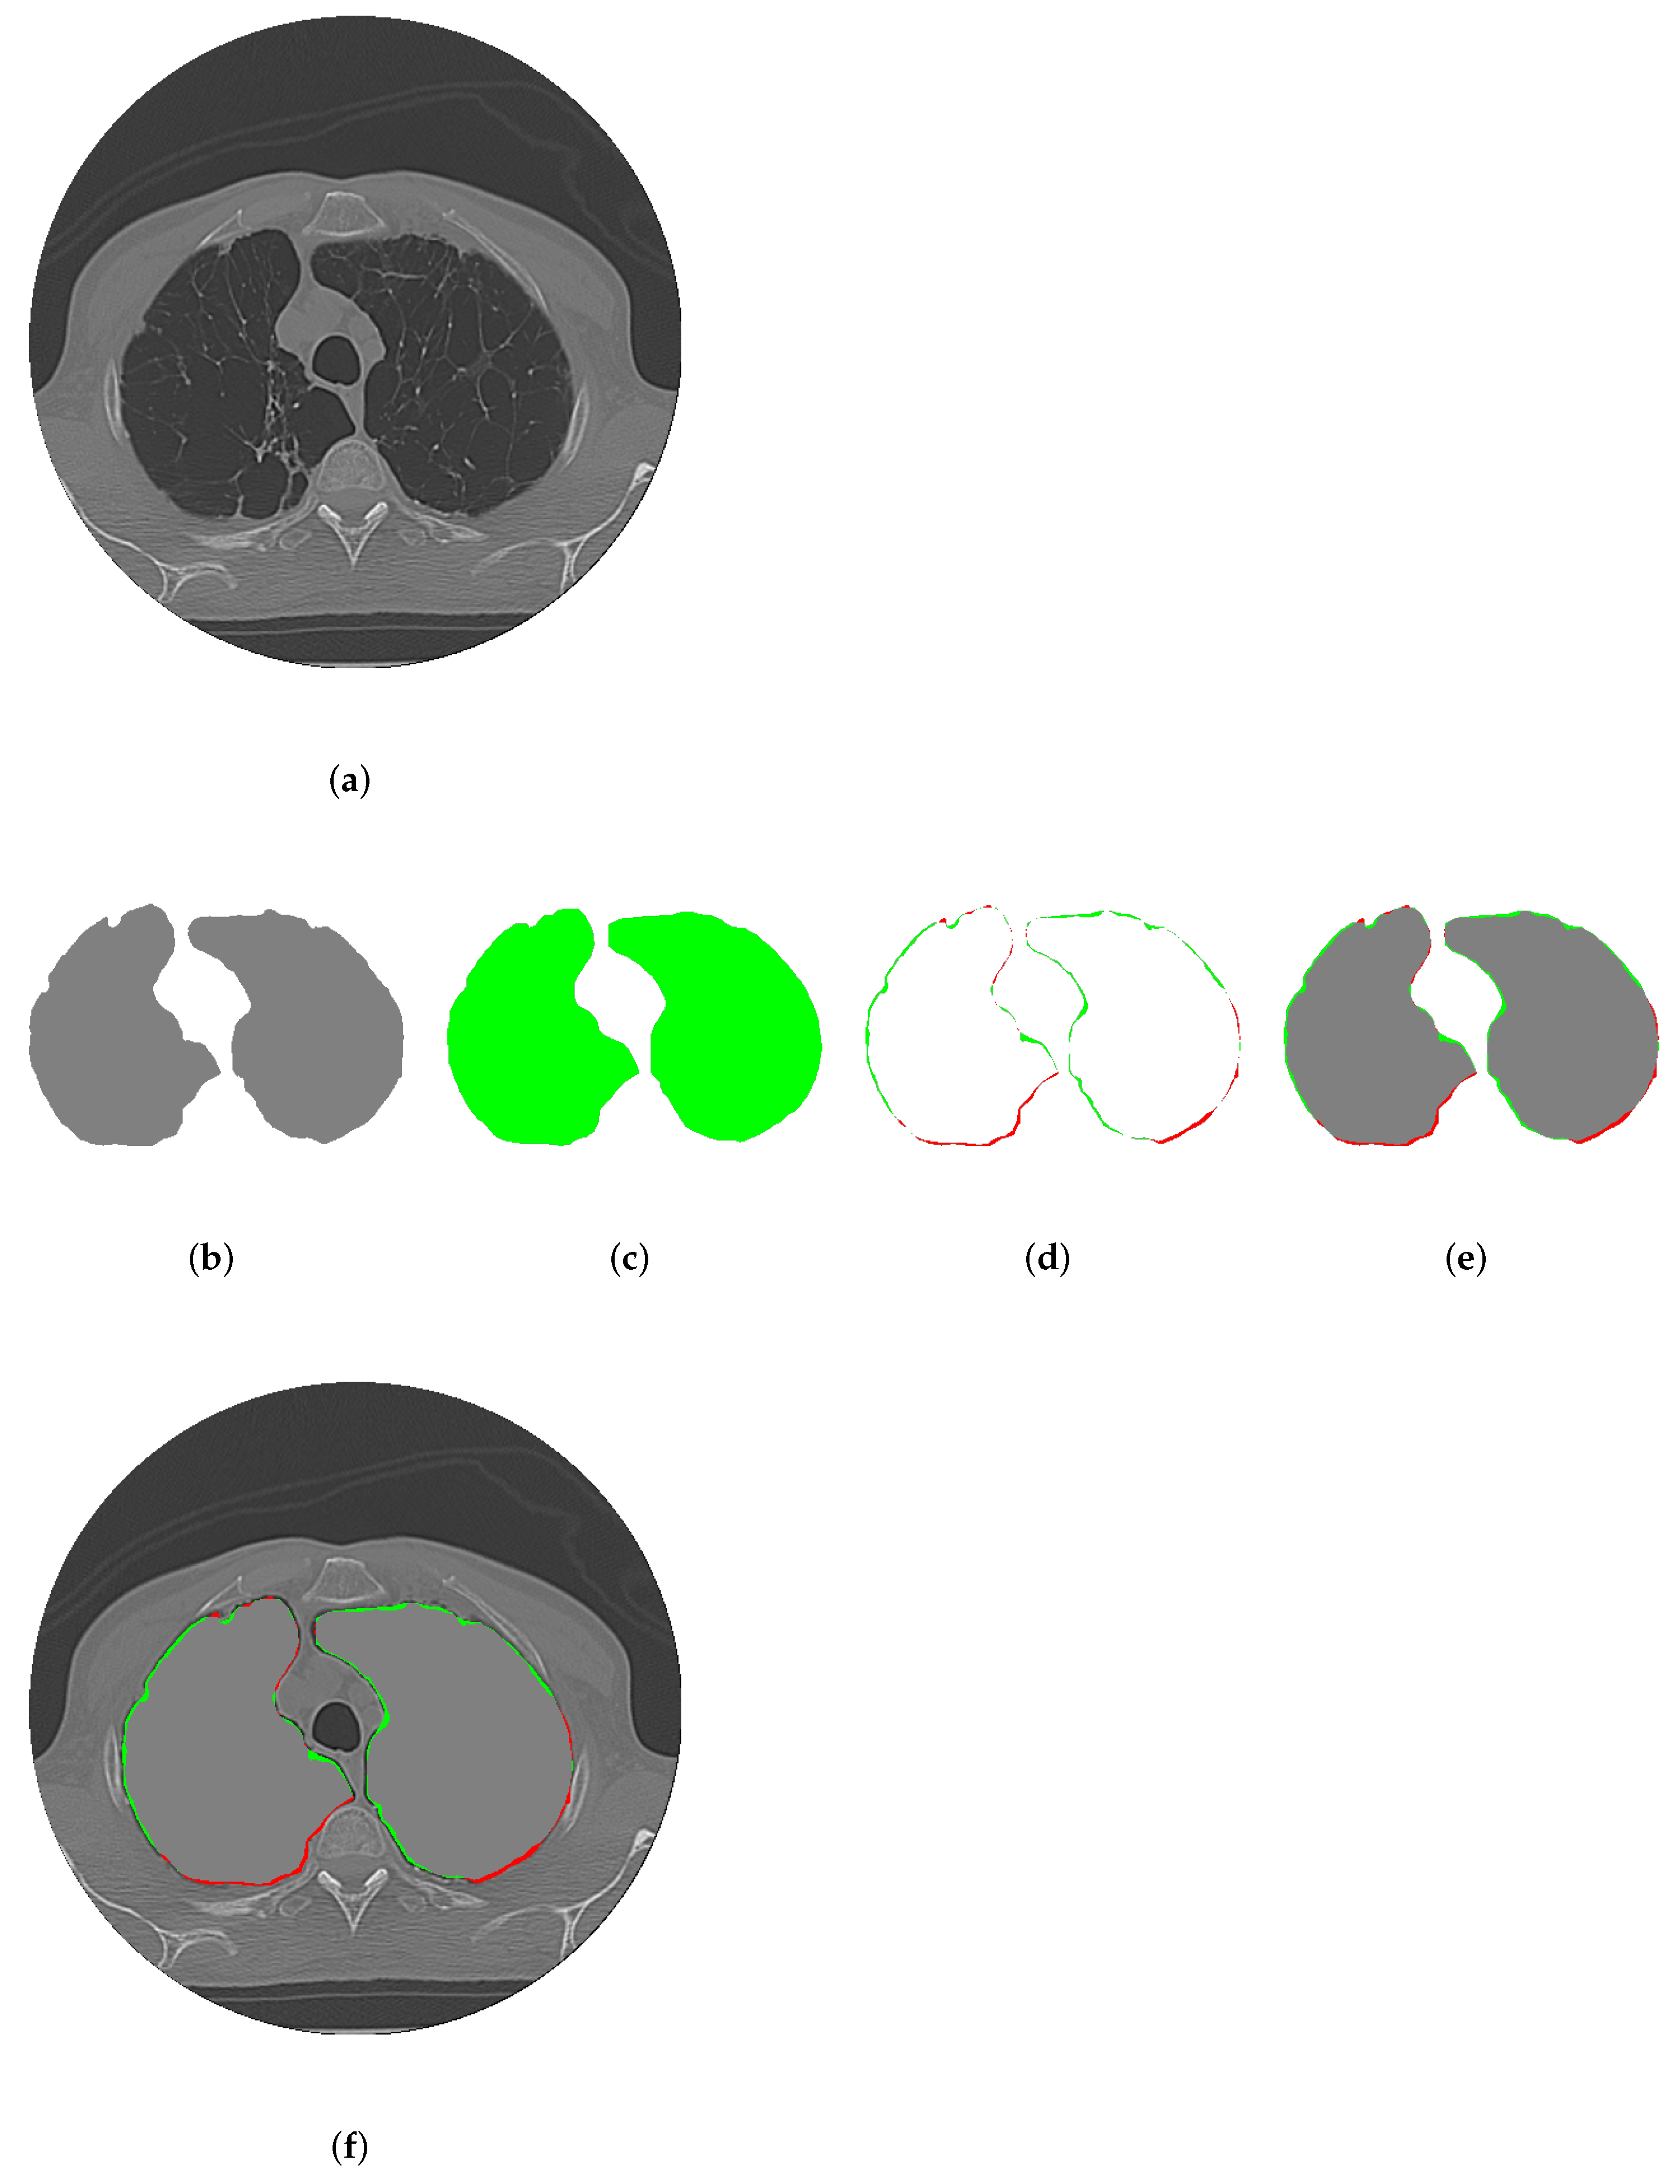

3.6. CDAC Segmentation Interpretability

- Expert-guided initialization: Radiologists can define an initial region of interest (ROI) by marking key areas in the image. This ensures that segmentation aligns with expert knowledge instead of relying exclusively on learned representations;

- Progressive contour evolution: The active contour model gradually adapts its boundaries based on predefined energy functions (CAF and CBF), allowing for visual tracking of the segmentation process, a feature typically absent in deep learning-based approaches;

- Context-aware decision making: Instead of solely depending on global pixel features, CDAC dynamically adjusts segmentation based on local image context, making it easier to interpret why a particular boundary was selected.